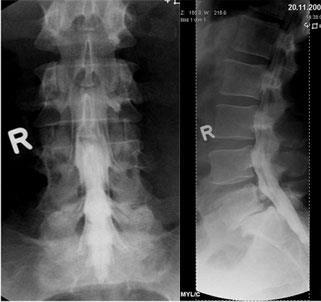

Dies sind Röntgenaufnahmen von derselben Stelle, die in verschiedenen Körperpositionen aufgenommen werden, bei der Wirbelsäule zumeist in Vor- und Rückneigung. Sie dienen der Diagnose von Gleitwirbeln.

Aufnahmen von der Wirbelsäule zur Beurteilung von Veränderungen am Knochen, vor Operationen, zum Ausschluß von Knochenbrüchen und zur Verlaufskontrolle. Eine spezielle Vorbereitung der Patienten ist nicht notwendig. Moderne Röntgengeräte fertigen solche Aufnahmen mit einer geringen Strahlendosis an. Für alle, die sich genauer über die Auswirkung von Strahlen informieren wollen, empfiehlt sich ein Blick in Wikipedia.